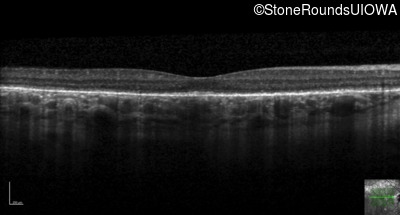

Age at visit: 33 years

Age at visit: 33 years (Visit 2)